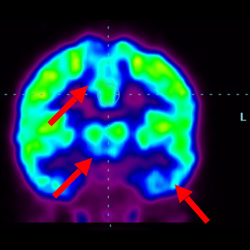

細(xì)胞治療前PET CT掃描顯示神經(jīng)組織中的藍(lán)/黑色區(qū)域,表明腦癱引起的大腦損傷。

腦癱細(xì)胞療法, 腦癱治療

細(xì)胞治療后,藍(lán)色和黑色區(qū)域減少,并且看到更活躍的區(qū)域。這表明損傷減少并改善了大腦功能。